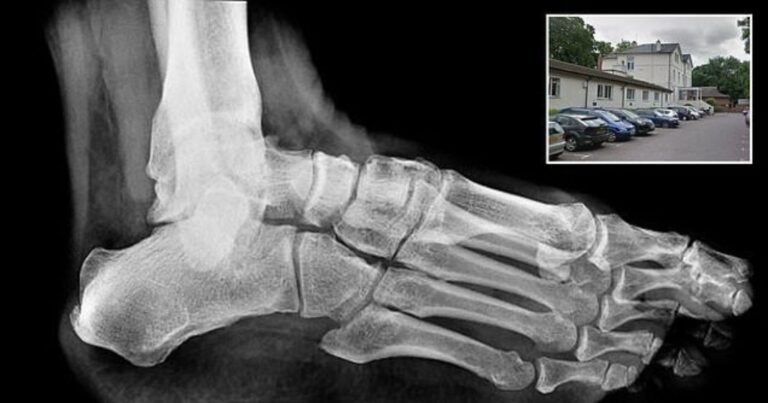

യുകെയിൽ റേഡിയോഗ്രാഫർ ആയി ചമഞ്ഞ് വൻ തട്ടിപ്പ് നടത്തി മലയാളി യുവതി..! നാട്ടിൽ റിസപ്ഷനിസ്റ്റ് !

യുകെയിൽ വ്യാജ റേഡിയോഗ്രാഫർ ആയി ചമഞ്ഞ് തട്ടിപ്പ് നടത്തി യുകെ ഇന്ത്യൻ യുവതി. സ്മിത ജോണി എന്ന യുവതിയാണ് തട്ടിപ്പിന് പിന്നിൽ. ഇവർ മലയാളിയാണ് എന്നാണ് പുറത്തുവരുന്ന വിവരം . എന്നാൽ കേരളത്തിൽ എവിടെയാണ് എന്നതിൽ വ്യക്തതയില്ല. തനിക്ക് നാട്ടിൽ 23 വർഷത്തെ ജോലി പരിചയമുള്ളതായി വ്യാജ സർട്ടിഫിക്കറ്റുകൾ തയ്യാറാക്കി റേഡിയോഗ്രാഫറായി ജോലി ചെയ്തു വരികയായിരുന്നു ഇവർ. ഇംഗ്ലീഷ് തന്റെ മാതൃഭാഷയാണെന്നും റേഡിയോഗ്രാഫിയിൽ രണ്ട് പതിറ്റാണ്ടിലേറെ പരിചയമുണ്ടെന്നും അവകാശപ്പെട്ടുകൊണ്ട് സ്മിത ജോണി 2021 ൽ ആണ് സ്മിത … Continue reading യുകെയിൽ റേഡിയോഗ്രാഫർ ആയി ചമഞ്ഞ് വൻ തട്ടിപ്പ് നടത്തി മലയാളി യുവതി..! നാട്ടിൽ റിസപ്ഷനിസ്റ്റ് !